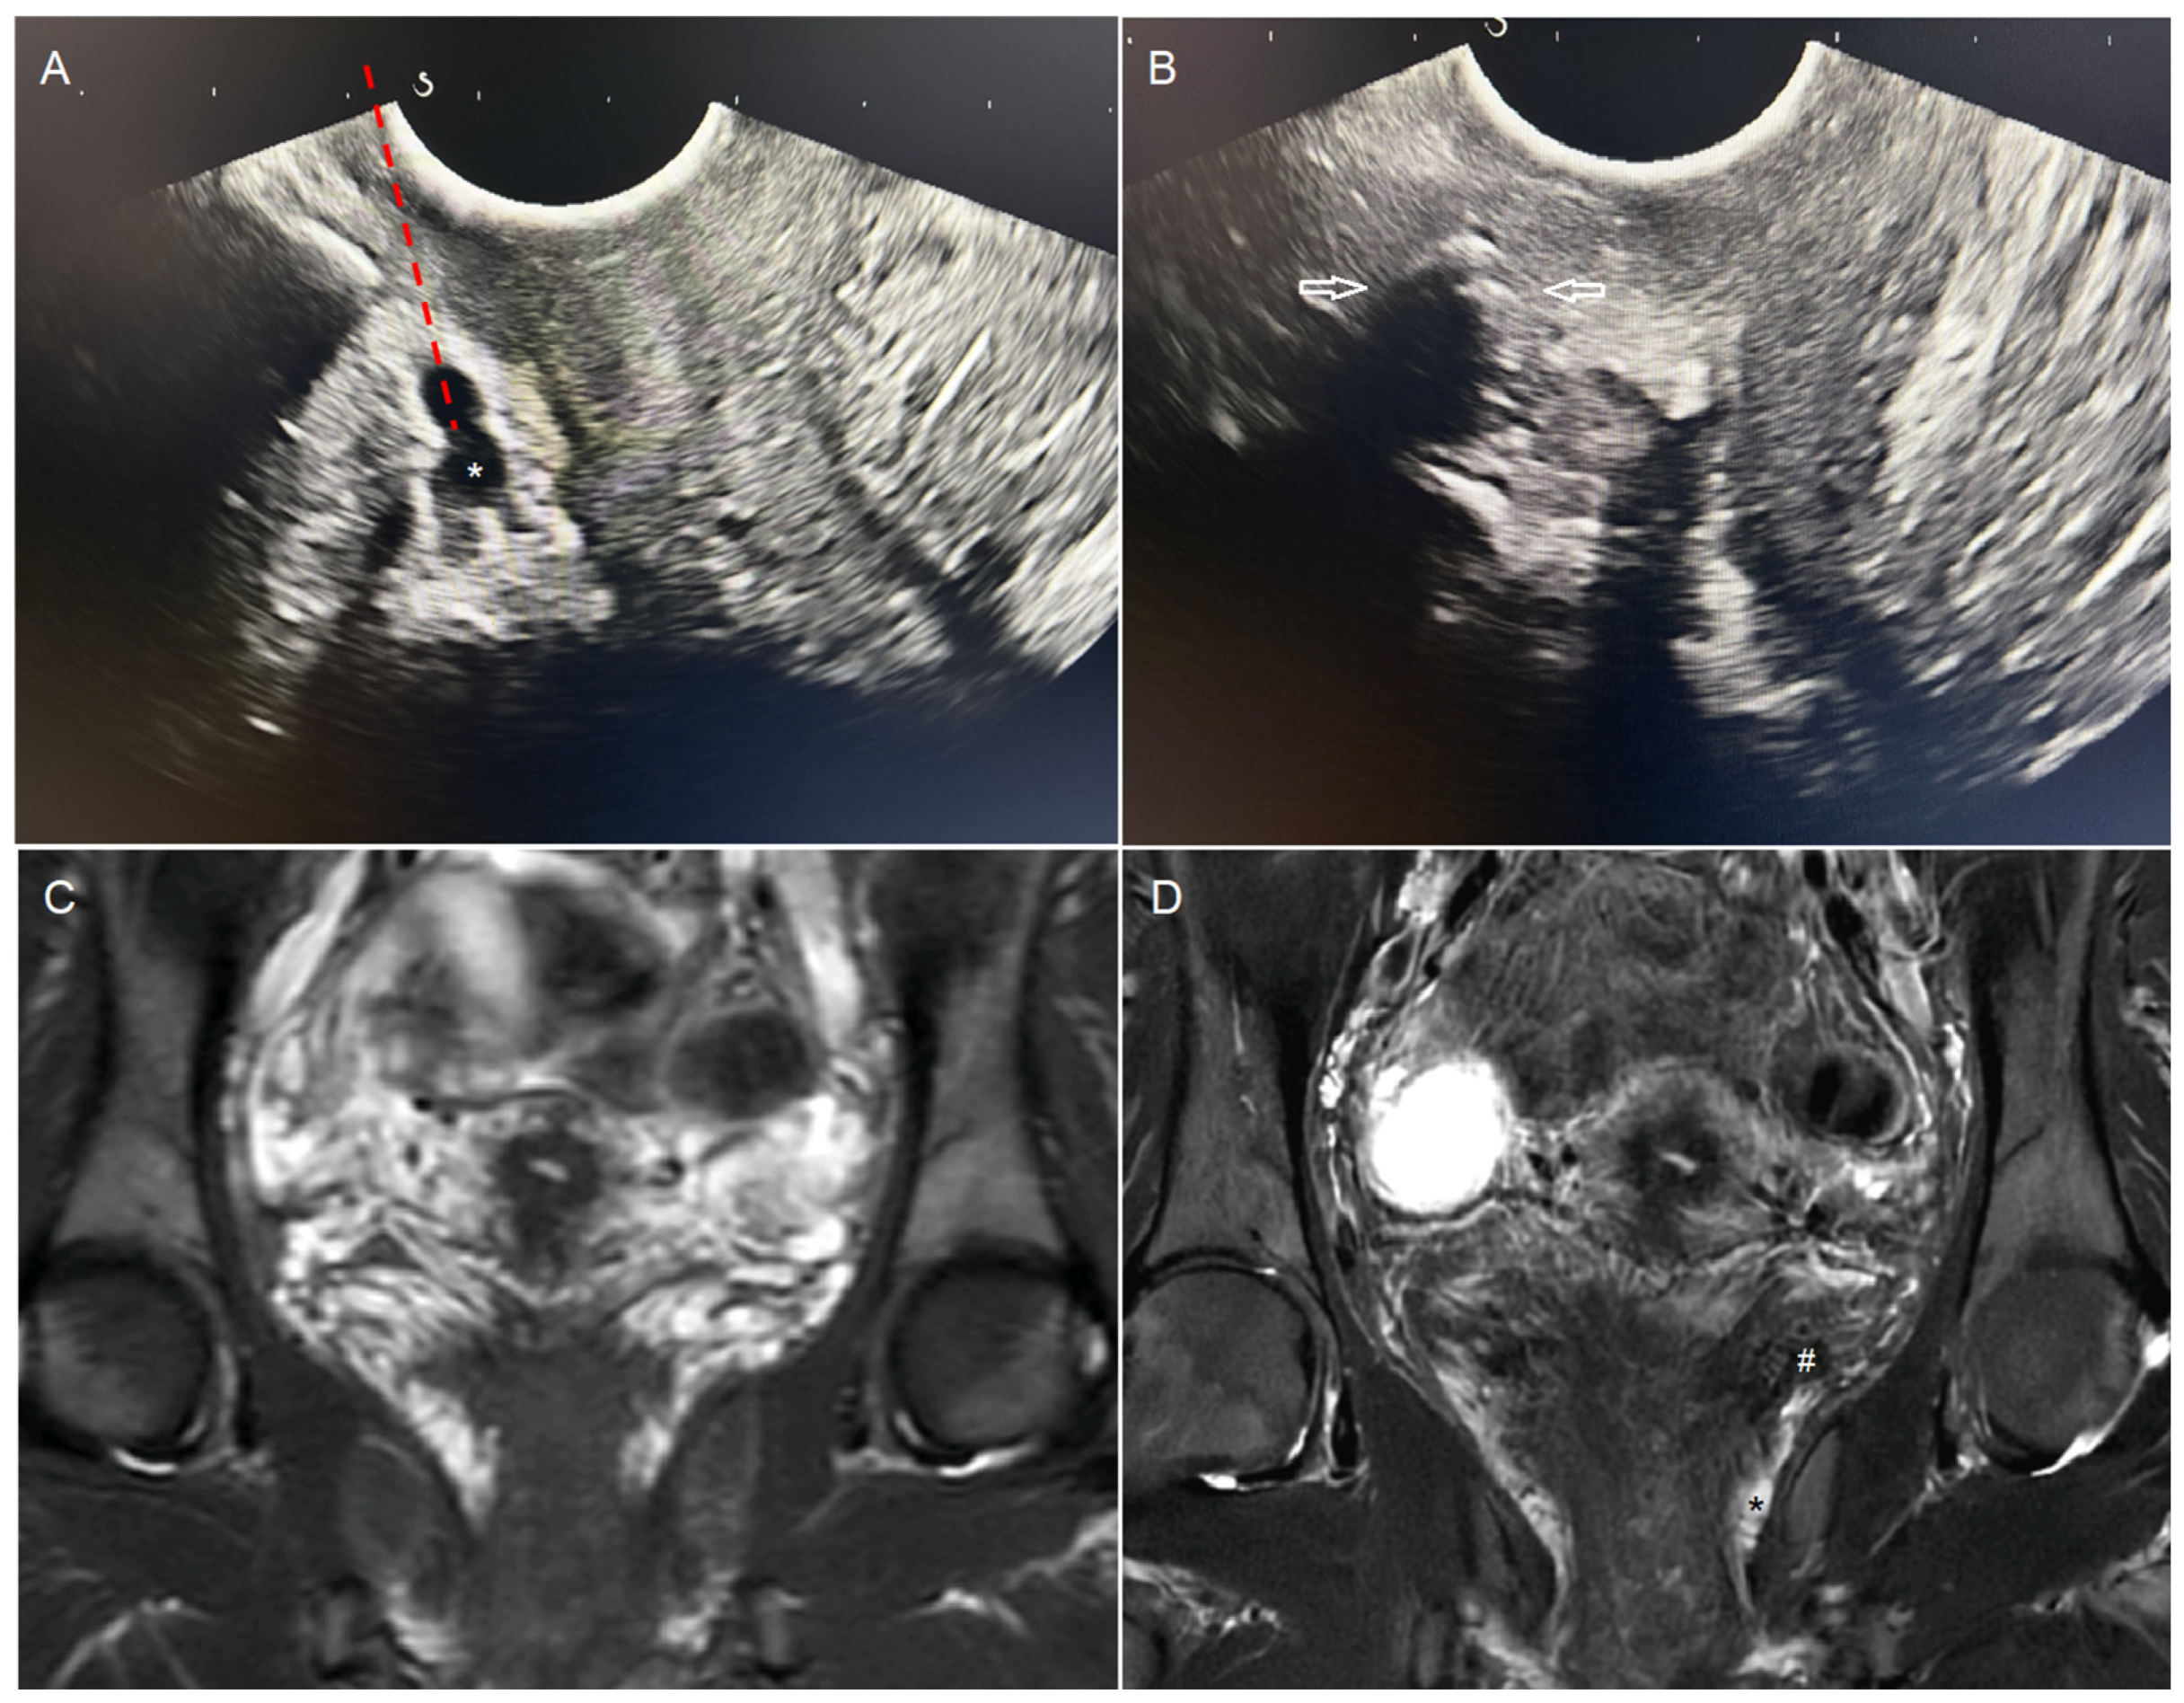

Figure 5. Comparison of ultrasound and MRI images before and after embolization. (A) Visualization of perivaginal varicosities (*) on endovaginal ultrasound. Simulated needle trajectory (---). (B) Same ultrasound image immediately after embolization. Attenuation artifact from the embolic agent with posterior acoustic shadowing (white arrows). (C) Pre-embolization MRI. Coronal T2 STIR sequence through the uterine torus and vagina. Multiple bilateral peri-uterine and perivaginal varicosities appear hyperintense. (D) MRI at 3 months after embolization by endovaginal guidance. Coronal T2 STIR sequence at the same level. Marked reduction in peri-uterine and perivaginal varicosities. Embolization material appears hypointense within the veins (#). Persistent dilated left perivaginal varices, though the patient was asymptomatic (*).

There were no major complication. One patient reported a minor complication consisting of transient dysuria, which resolved spontaneously in less than a week (1/10, 10%). Imaging follow-up showed a significant reduction in perivaginal varicosities in all cases (100%) (Figure 5).